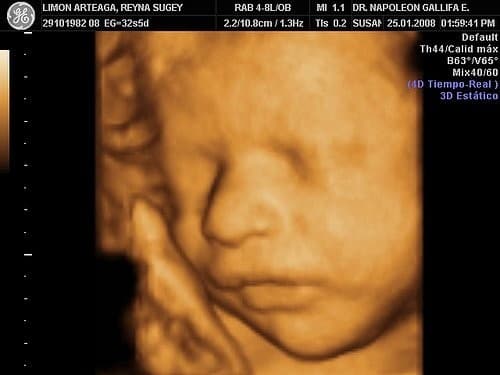

Siêu âm thai 4D đem lại lợi ích gì và các mốc siêu âm thai 4D là thế nào? Chắc chắn rằng những thông tin sau đây của chúng tôi rất hữu ích với bạn. 1. Siêu âm thai 4D là gì? Những lợi ích của hình thức siêu âm 4D Siêu âm thai 4D […]